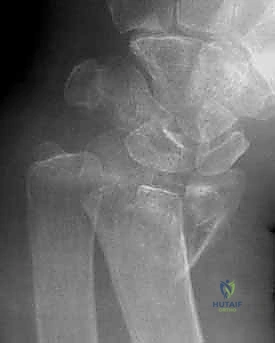

تُعرف كسور الكعبرة البعيدة بأنها تشمل منطقة الكردوس (Metaphysis)، وتحديداً المنطقة الواقعة ضمن طول السطح المفصلي الذي يعادل أوسع جزء من الرسغ بأكمله. في عياداتنا، نقوم بتقييم هذه الكسور بدقة متناهية بناءً على عدة خصائص رئيسية تحدد مسار العلاج:

- امتداد الكسر: هل هو خارج المفصل (Extra-articular) أم داخل المفصل (Intra-articular)؟

- درجة التفتت: هل العظم مكسور إلى قطعتين أم مفتت إلى عدة شظايا؟

يعتمد الدكتور محمد هطيف على أحدث التقنيات التشخيصية، حيث يبدأ بـ الأشعة السينية (X-rays) في وضعيات متعددة. وفي حالات الكسور المعقدة التي تمتد إلى داخل المفصل، يتم إجراء تصوير مقطعي محوسب (CT Scan) لبناء صورة ثلاثية الأبعاد للكسر، مما يساعد في التخطيط الجراحي الدقيق.